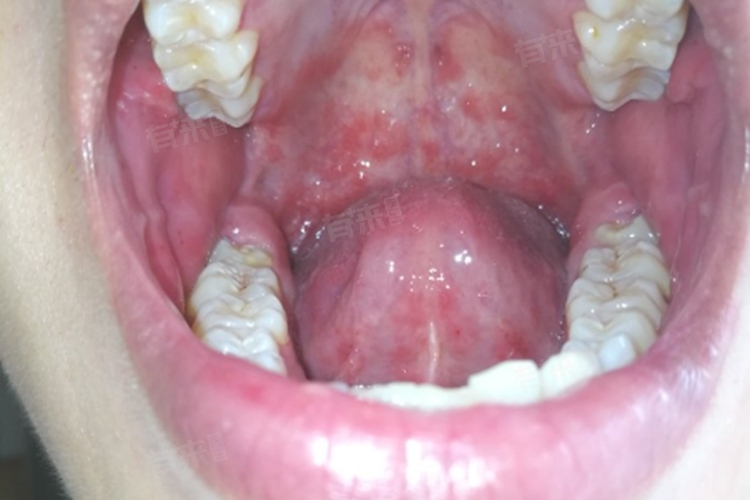

上牙膛出现小疙瘩是一种口腔现象,其背后的成因较为复杂,涉及多个方面,具体包括过烫食物刺激、食物过敏、口腔溃疡、口腔疱疹等。

4、口腔疱疹:由单纯疱疹病毒感染引起的口腔疱疹,也可能导致上牙膛出现小疙瘩。病毒入侵口腔黏膜后,会在局部大量繁殖,引发炎症反应,使黏膜出现成簇的小水疱,这些水疱看起来就像小疙瘩。水疱容易破裂,形成浅表溃疡,伴有疼痛、灼热感,还可能出现发热、乏力等全身症状。

另外,还可能是手足口病。此类情况多发生于儿童,由肠道病毒引起。除了手、足、口腔等部位出现疱疹外,上牙膛也可能出现小疙瘩。这些小疙瘩起初为红色丘疹,随后会发展为水疱,周围有红晕,患者还可能伴有发热、咳嗽、流涕、食欲不振等症状。手足口病具有一定的传染性,需要及时隔离治疗。

- 医生通过肉眼直接观察上牙膛小疙瘩的形态、大小、颜色、数量、分布情况等。查看小疙瘩是水疱、丘疹还是溃疡,表面是否光滑,周围黏膜是否有充血、水肿等,初步判断小疙瘩的性质。